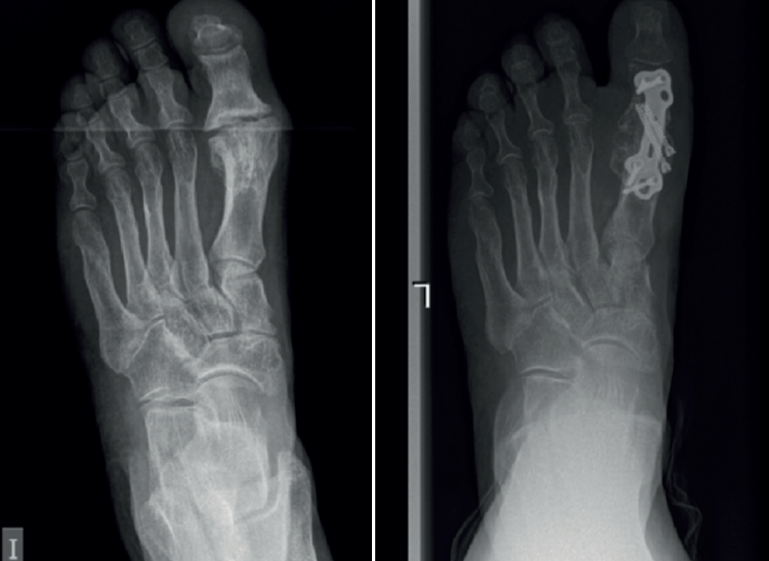

Entre febrero de 2022 y junio de 2023, hubo 7 procedimientos de este tipo realizados por el primer autor. Había 6 mujeres y 1 hombre, con una edad media de 64,8 años (rango: 56-71) en el momento de la cirugía (Tabla 1). No se excluyó a ningún paciente del estudio y ninguno se perdió durante el seguimiento. De los pacientes, 5 sufrían dolor (sin fusión) tras el fracaso de una artrodesis de la MTF1 previa con pérdida ósea limitada (Figura 1); 2 pacientes sufrieron dolor debido a hallux elevatus y en valgo tras una artrodesis de la MTF1 con consolidación viciada (Figura 2).